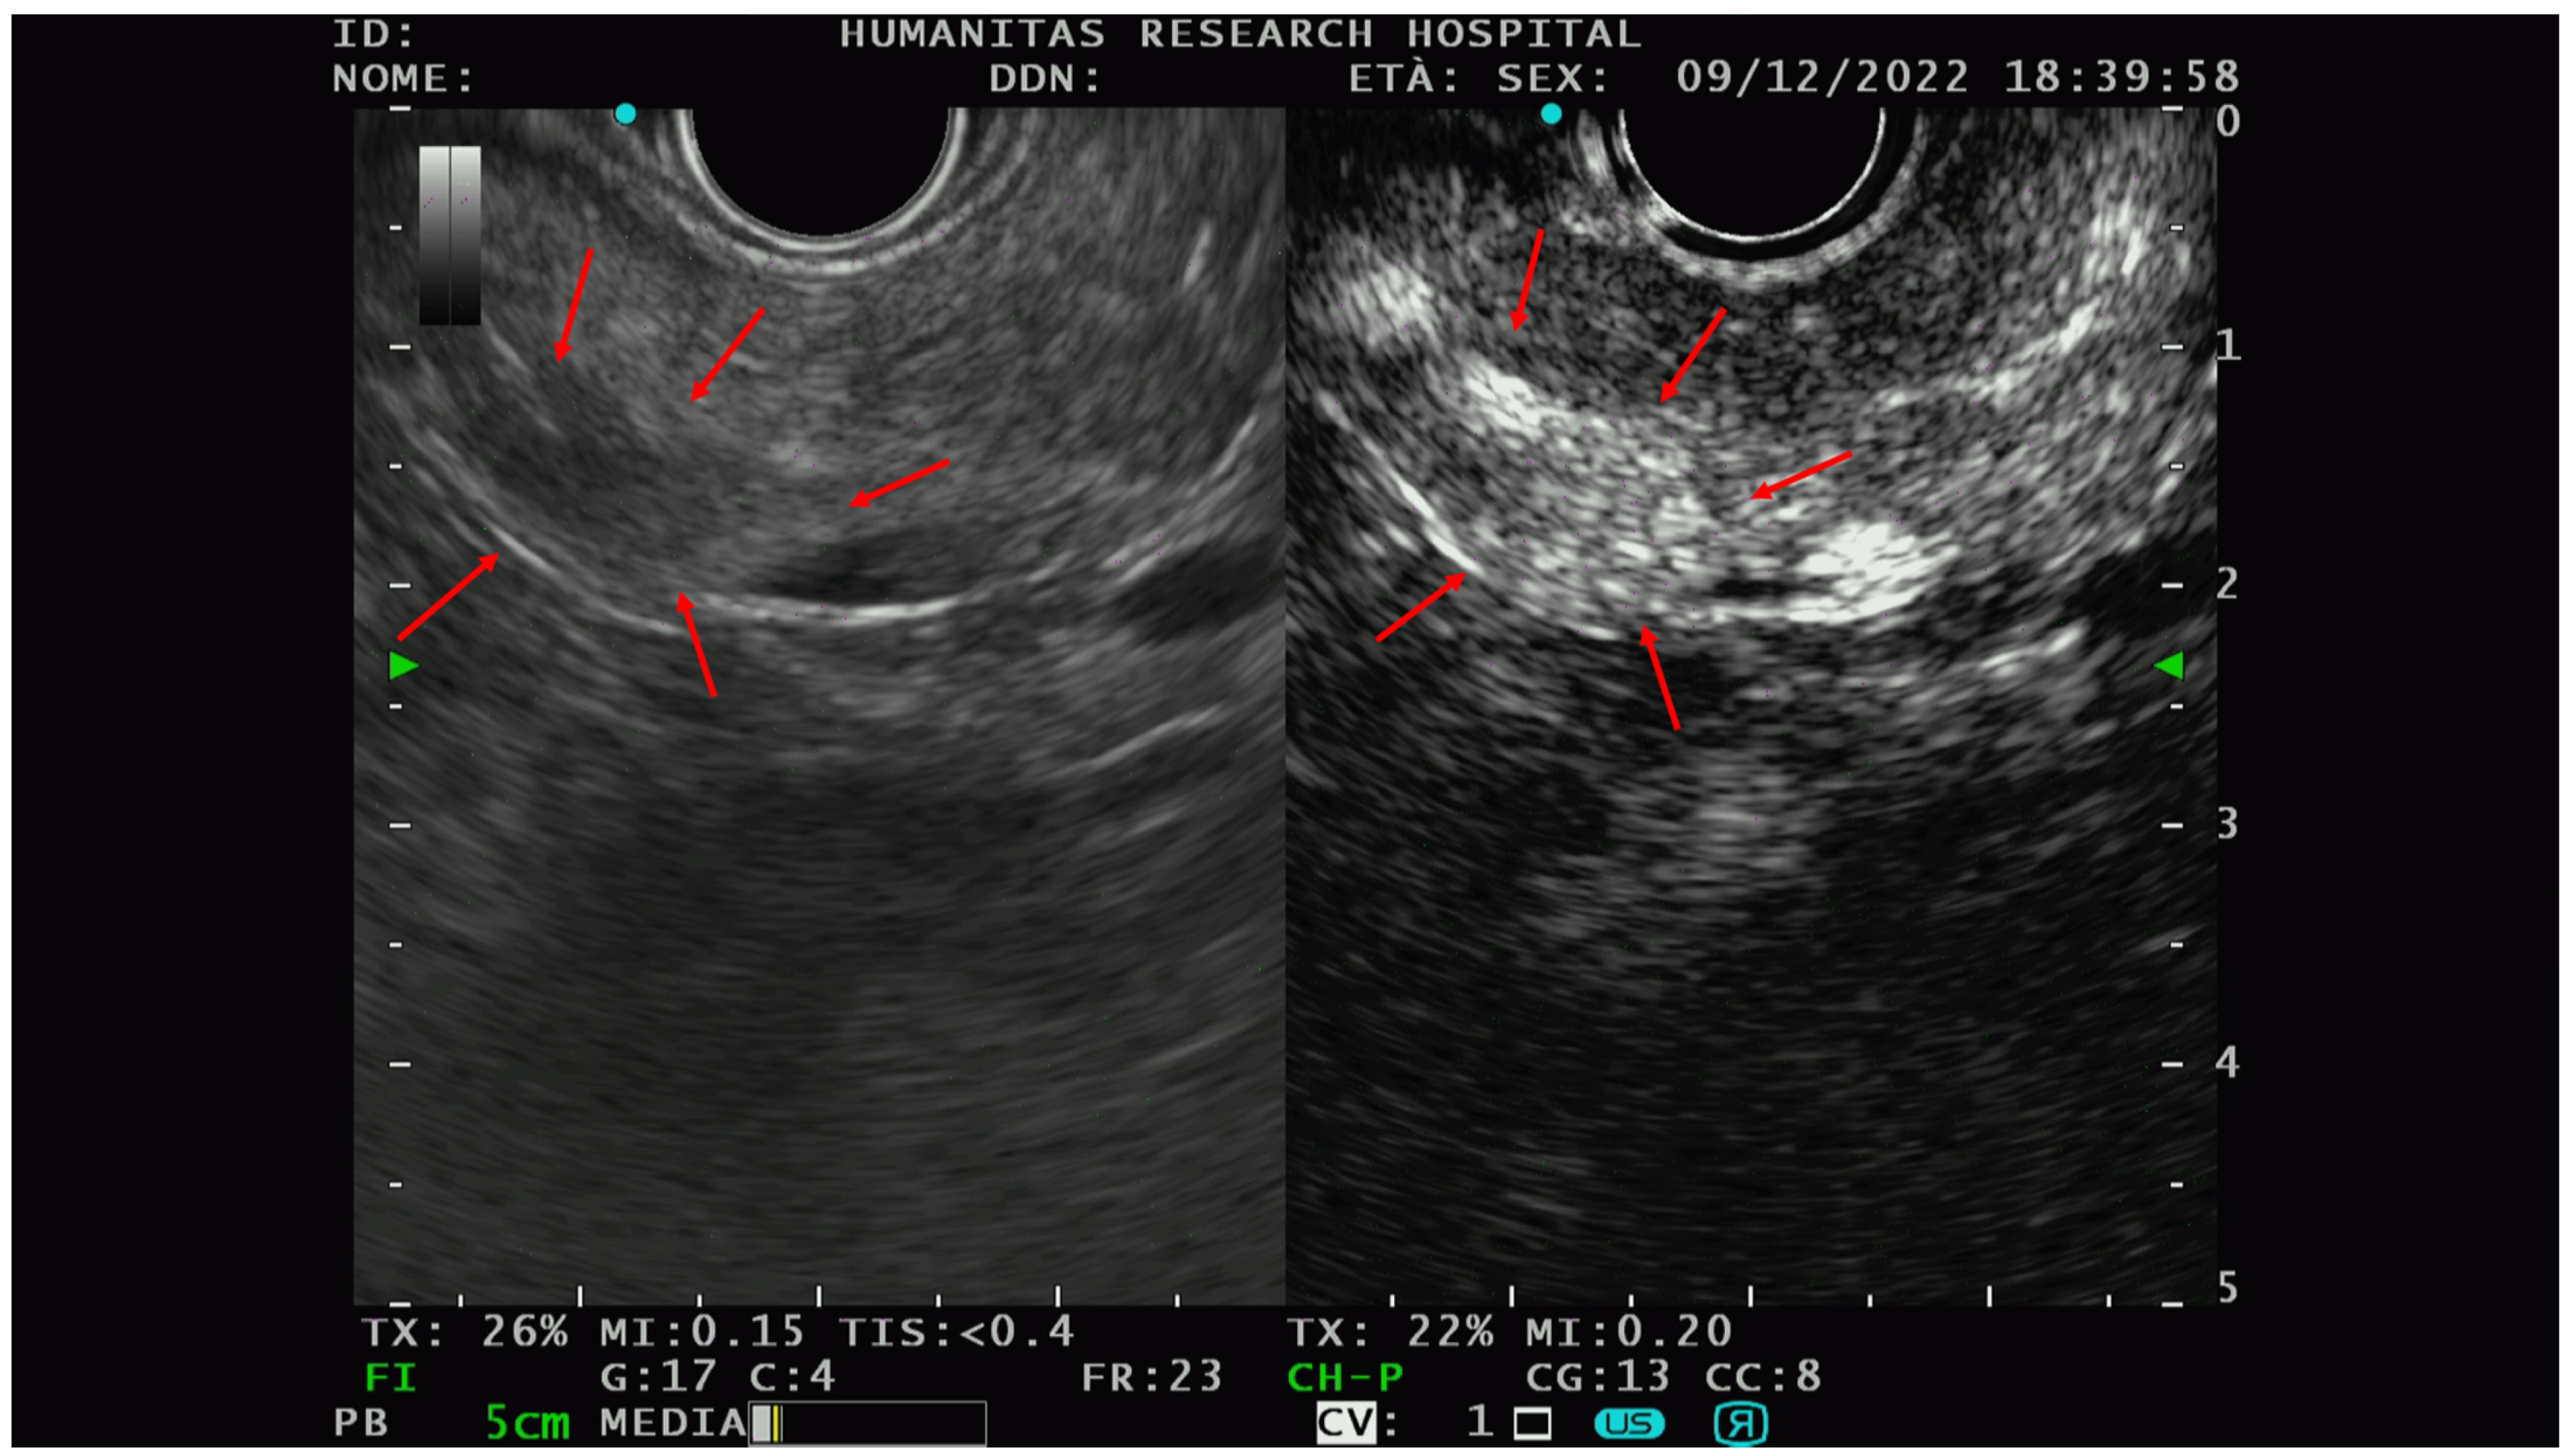

The PNETs typically show hyperenhancement (Figure 3) on CE-EUS, even when very small in size, and are therefore difficult to detect on basal scans [47].

Figure 3.

An example of the PNET EUS appearance with and without contrast (Sonovue). In the right picture, there is a hypo-isoechoic lesion while in the picture on the left, the hyperenhancement of the same lesion could be appreciated after intravenous contrast administration. Red arrows delineate the edge of the lesions. After FNAB, the solid lesion was characterized as G1-PNET.